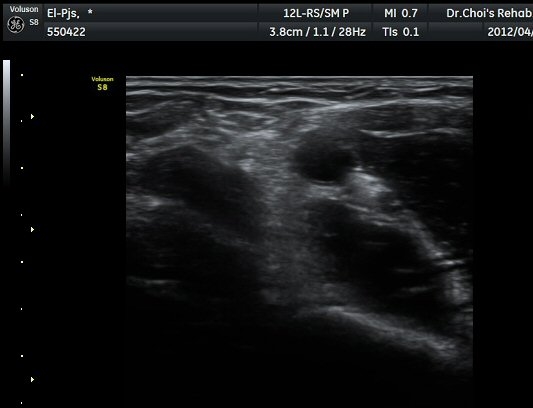

ÆÈ²ÞÄ¡ ¾ÕÂÊ È²µò¸é°Ë»ç¿¡¼­ Á¤»óÀûÀ¸·Î À̵ιڱ٠ÈûÁÙ°ú »ó¿Ïµ¿¸ÆÀÌ °üÂûµÈ´Ù(±×¸² 1).

ŽÃËÀÚ¸¦ ÆÈ²ÞÄ¡ ¸»´ÜÀ¸·Î À̵¿ÇÏ´Ï À̵ιڱ٠ÈûÁÙÀÇ ºñÈÄ¿Í ÈûÁÙ ÁÖÀ§¿¡ Àú¿¡ÄÚ ¼ö¾×Àú·ù°¡ ]

°üÂûµÈ´Ù(±×¸² 2, 3, 4, 5). ŽÃËÀÚ¸¦ ¸»´ÜÀ¸·Î À̵¿ÇÒ ¶§ ŽÃËÀÚ¸¦ ¸Ó¸®ÂÊÀ¸·Î °æ»ç(tilting)½ÃÄѾß

À̵ιڱ٠ÈûÁÙ¿¡ Á÷°¢ ÀÇ ÃÊÀ½ÆÄ Á¶»ç°¡ °¡´ÉÇÏ¿© À̵ιڱ٠ÈûÁÙÀÌ °í¿¡ÄÚ·Î °üÂûµÈ´Ù.